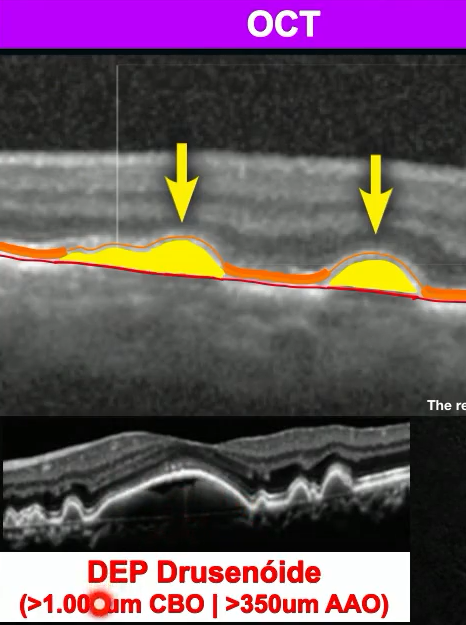

Achados no OCT? (2)

A

1. Depósito entre EPR e coriocapilar com EPR afilada. (EPR mais longe da nutrição)

2. DEP drusenóide: >1000 CBO/ >350 AAO. (Drusas confluindo e descolando boa parte do EPR)

Definição segundo CBO e AAO? Mecanismo? Risco?

1. > 1000 CBO/ >350 AAO.

2. Drusas confluindo e descolando boa parte do EPR.

3. Risco para DMRI avançada maior pois EPR sofre mais.